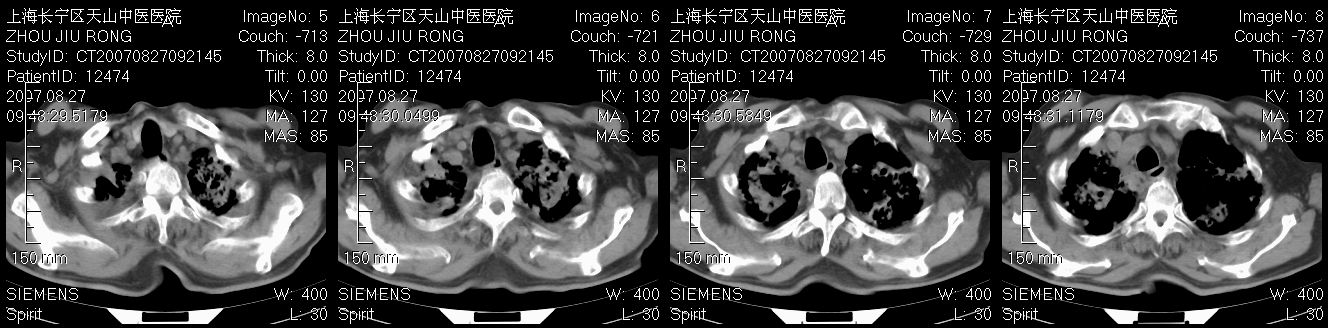

以下是引用zjzjr在2007-8-30 21:47:00的发言:[br]双肺弥漫性结节状、斑片状影,部分形成空洞,病灶以双肺上叶为著(符合结核发病部位),纵隔内见肿大淋巴结影。支持双肺继发性结核伴右上肺空洞形成。

以下是引用zjzjr在2007-8-30 21:47:00的发言:[br]双肺弥漫性结节状、斑片状影,部分形成空洞,病灶以双肺上叶为著(符合结核发病部位),纵隔内见肿大淋巴结影。支持双肺继发性结核伴右上肺空洞形成。

以下是引用gaoshengjiang在2007-8-31 10:24:00的发言:[br]双肺弥漫性斑片状影及多发空洞影,其间夹杂多量条索状影,胸膜肥厚、粘连并有结节状改变,纵隔多枚淋巴结肿大,考虑1双肺继发型肺结核合并感染?2韦格氏肉芽肿?[br] 支持!

以下是引用zjzjr在2007-8-30 21:47:00的发言:[br]双肺弥漫性结节状、斑片状影,部分形成空洞,病灶以双肺上叶为著(符合结核发病部位),纵隔内见肿大淋巴结影。支持双肺继发性结核伴右上肺空洞形成。

以下是引用zjzjr在2007-8-30 21:47:00的发言:[br]双肺弥漫性结节状、斑片状影,部分形成空洞,病灶以双肺上叶为著(符合结核发病部位),纵隔内见肿大淋巴结影。支持双肺继发性结核伴右上肺空洞形成。

以下是引用zjzjr在2007-8-30 21:47:00的发言:[br]双肺弥漫性结节状、斑片状影,部分形成空洞,病灶以双肺上叶为著(符合结核发病部位),纵隔内见肿大淋巴结影。支持双肺继发性结核伴右上肺空洞形成。